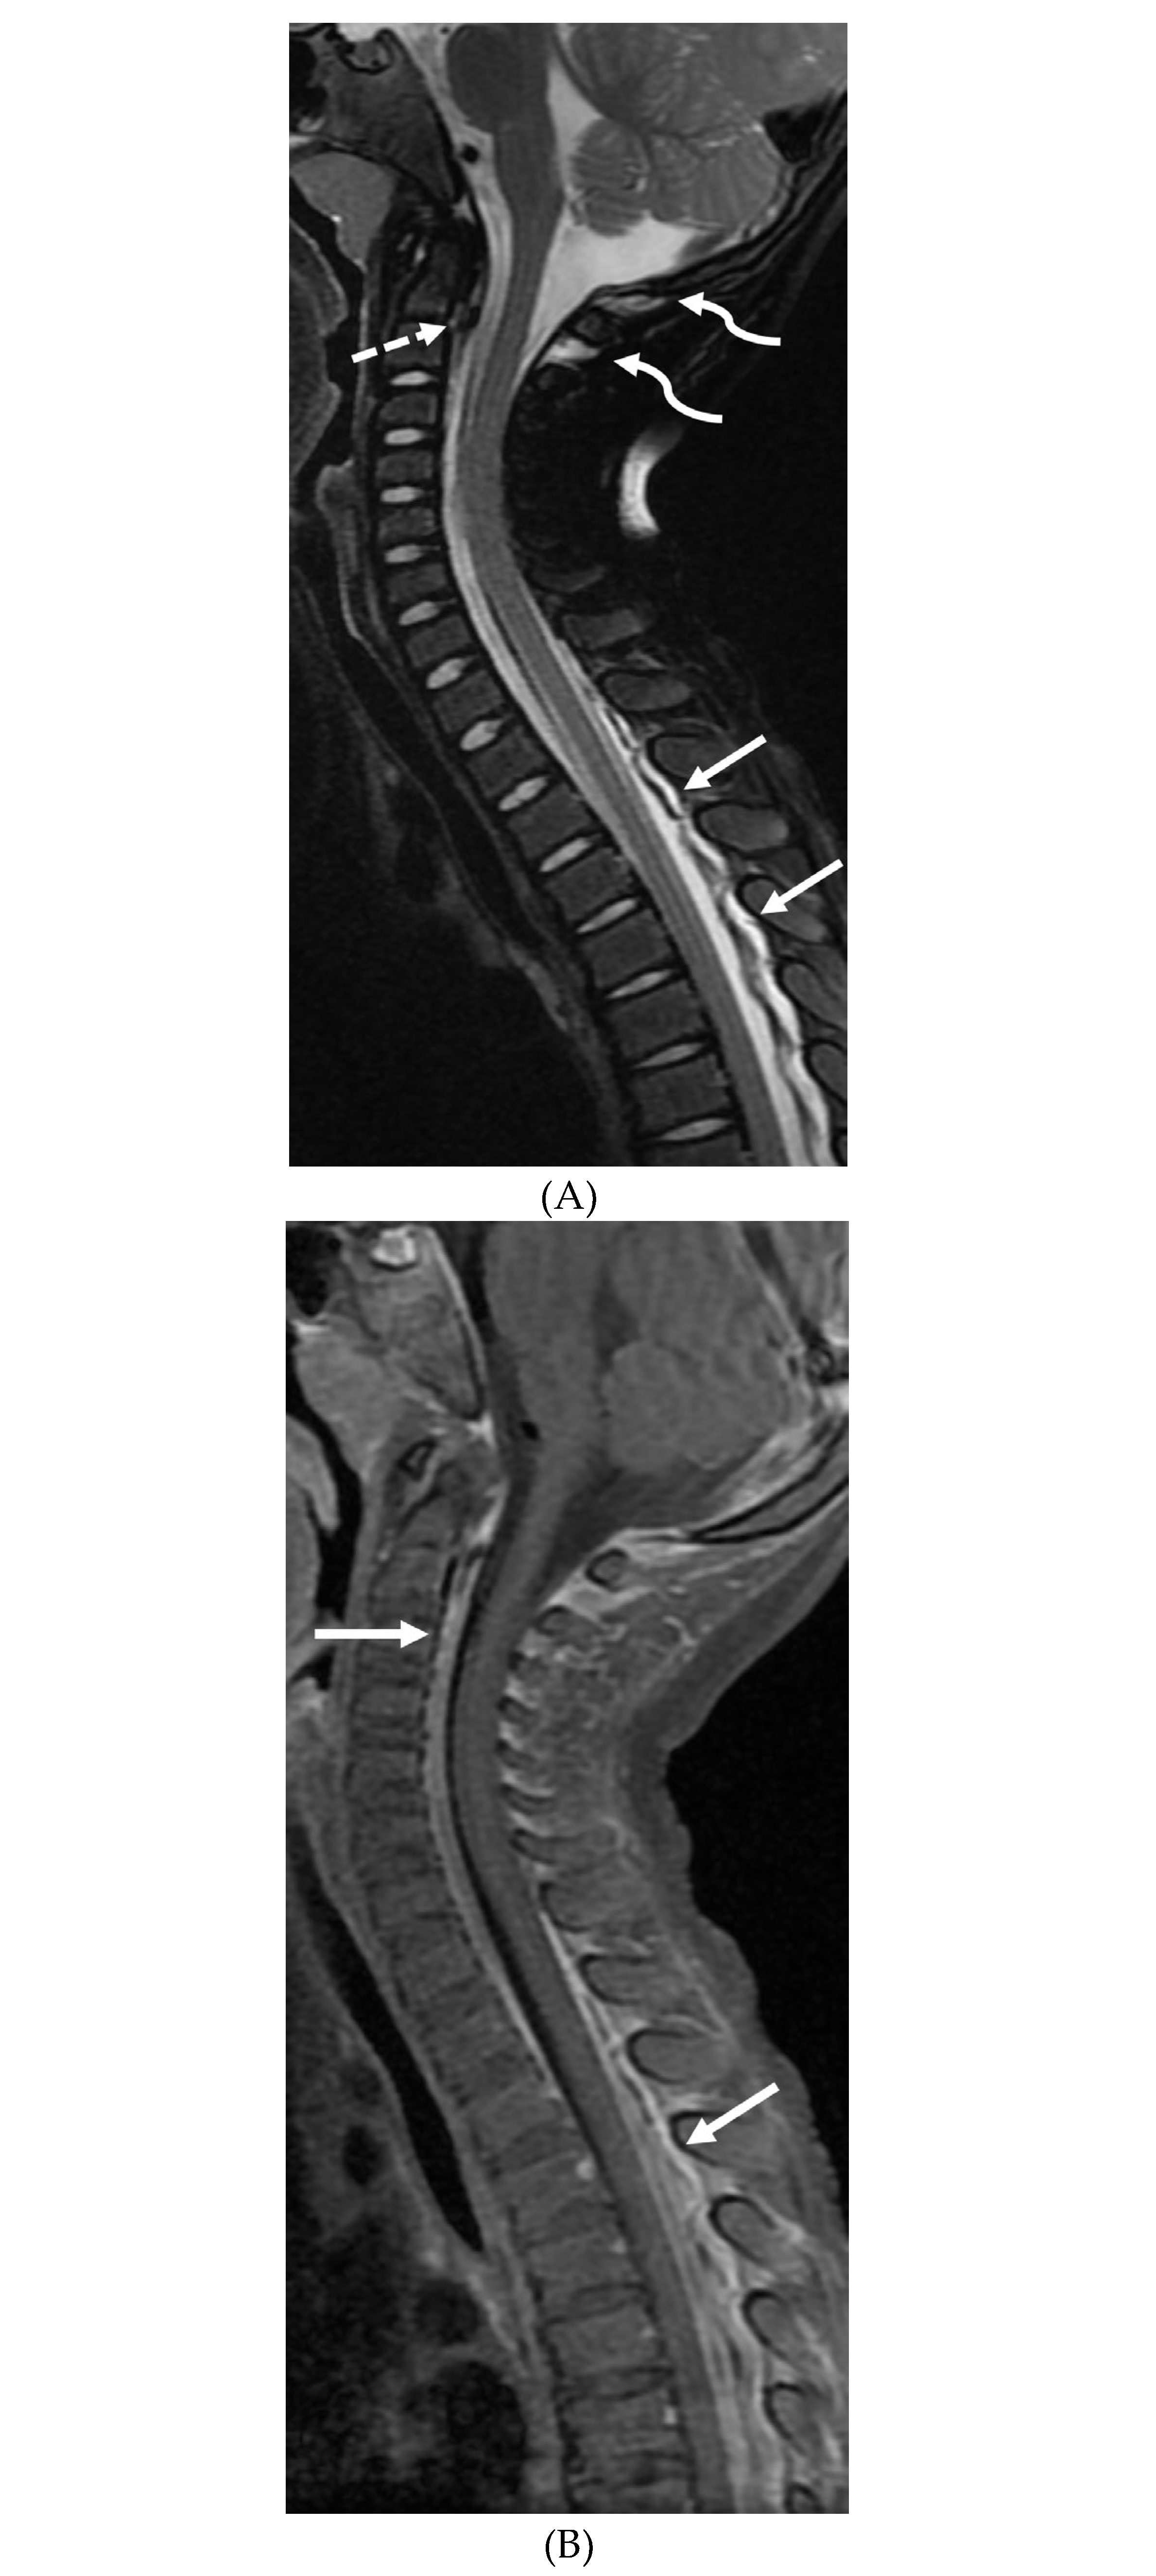

MOYA MOYA

- Liu ZW, Han C, Zhao F, Qiao PG, Wang H, Bao XY, Zhang ZS, Yang WZ, Li DS, Duan L. Collateral Circulation in Moyamoya Disease: A New Grading System. Stroke. 2019 Oct;50(10):2708-2715. Epub 2019 Aug 14. PMID: 31409266. [CrossRef]

- Tajmalzai A, Shirzai A, Najah DM. Early manifestation of Moyamoya syndrome in a 2-year-old child with Down syndrome. Radiol Case Rep. 2021 May 1;16(7):1740-1744. PMID: 34007395; PMCID: PMC8111440. [CrossRef]

- Horie N, Morikawa M, Nozaki A, Hayashi K, Suyama K, Nagata I. "Brush Sign" on susceptibility-weighted MR imaging indicates the severity of moyamoya disease. AJNR Am J Neuroradiol. 2011 Oct;32(9):1697-702. Epub 2011 Jul 28. PMID: 21799039; PMCID: PMC7965393. [CrossRef]

- Ohta T, Tanaka H, Kuroiwa T. Diffuse leptomeningeal enhancement, "ivy sign," in magnetic resonance images of moyamoya disease in childhood: case report. Neurosurgery. 1995 Nov;37(5):1009-12. PMID: 8559324. [CrossRef]

- Maeda M, Tsuchida C. "Ivy sign" on fluid-attenuated inversion-recovery images in childhood moyamoya disease. AJNR Am J Neuroradiol. 1999 Nov-Dec;20(10):1836-8. PMID: 10588105; PMCID: PMC7657767.

- Liu ZW, Han C, Wang H, Zhang Q, Li SJ, Bao XY, Zhang ZS, Duan L. Clinical characteristics and leptomeningeal collateral status in pediatric and adult patients with ischemic moyamoya disease. CNS Neurosci Ther. 2020 Jan;26(1):14-20. Epub 2019 Apr 13. PMID: 31875482; PMCID: PMC6930821. [CrossRef]

- Komiyama M, Nakajima H, Nishikawa M, Yasui T, Kitano S, Sakamoto H. Leptomeningeal contrast enhancement in moyamoya: its potential role in postoperative assessment of circulation through the bypass. Neuroradiology. 2001 Jan;43(1):17-23. PMID: 11214642. [CrossRef]